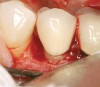

Figure 11  Very large osseous lesion exposed on tooth No. 22 after scaling and degranulation.

Figure 11